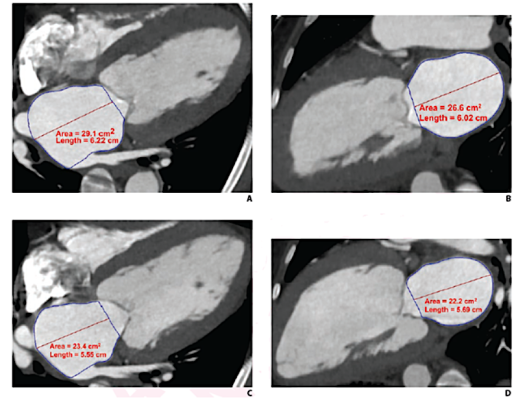

Cardiac CTA derived left atrium emptying fraction (LAEF) improves predictive performance of established clinical risk scores and may be used to assess TAVR patient risk during pre-procedure workup and post-procedural surveillance. These images show LAVmax (A and B), LAVmin (C and D), and LAEF using cardiac CTA. LAEF was calculated as (LAVmax-LAVmin)/LAVmax x 100. Given LAVmax of 109 mL and LAVmin of 80 mL, the LAEF was calculated to be 27%. Image courtesy of AJR.

Schoepf and colleagues’ retrospective single-center study included 175 patients with severe aortic stenosis (92 male, 83 female; median age, 79 years) who underwent cardiac CTA for clinical pre-TAVR assessment. Maximum and minimum left atrium volumes were calculated using biplane area-length measurements, and the values were indexed to body surface area: LAVImax and LAVImin, respectively.